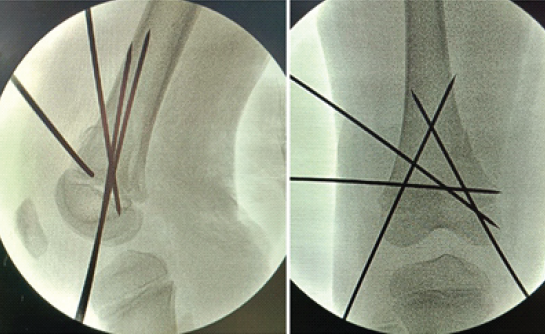

It was planned to attempt a closed reduction and stabilize the fracture with smooth Kirschner wires. The patient was posted for surgery in the emergency operating theatre on the same day. Under general anesthesia, the fracture was reduced with traction, countertraction, and gentle manipulation under C arm guidance (Fig 3).

Figure 3: Intraoperative C-arm image showing good reduction.

It was then stabilized with smooth K wires, as shown in intraoperative C-arm images, and an above-knee plaster of Paris slab was applied (Fig. 4).

Figure 4: Intraoperative C-arm image showing adequate reduction.